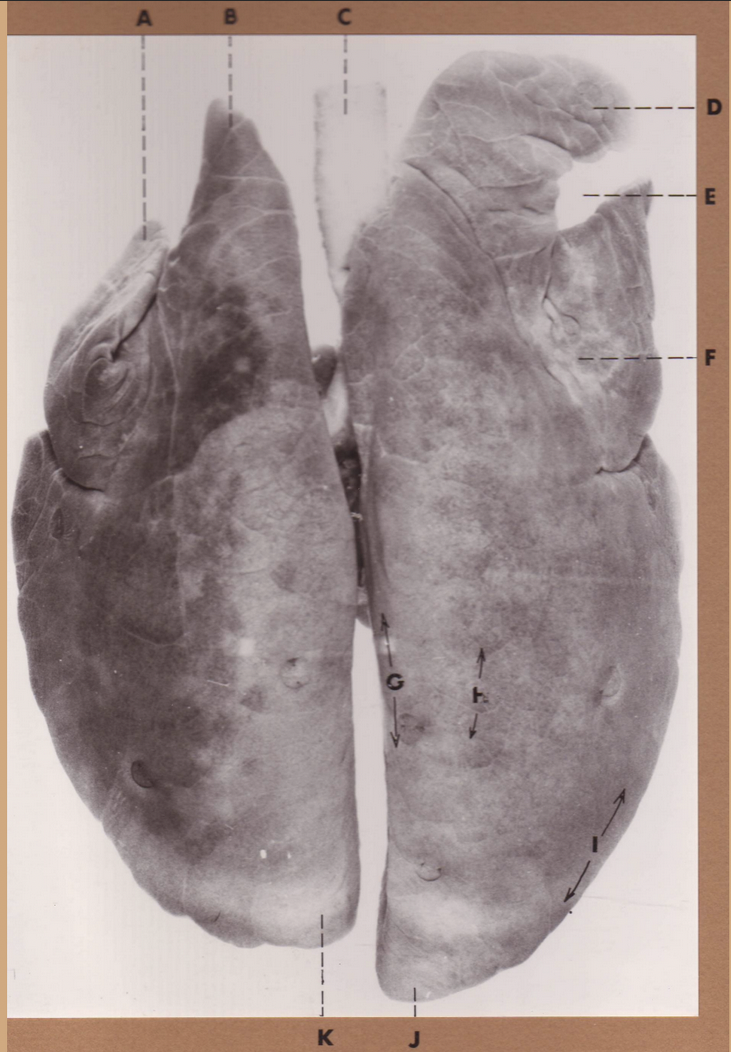

A

(cat larynx/trachea/lungs, dorsal)

epiglottis

B

(cat larynx/trachea/lungs, dorsal)

larynx

C

(cat larynx/trachea/lungs, dorsal)

trachea

D

(cat larynx/trachea/lungs, dorsal)

R cranial lobe

E

(cat larynx/trachea/lungs, dorsal)

middle lobe

F

(cat larynx/trachea/lungs, dorsal)

R caudal lobe

G

(cat larynx/trachea/lungs, dorsal)

primary bronchi

H

(cat larynx/trachea/lungs, dorsal)

L caudal lobe

I

(cat larynx/trachea/lungs, dorsal)

L cranial lobe

J

(cat larynx/trachea/lungs, dorsal)

cricoarytenoideus dorsalis m

K

(cat larynx/trachea/lungs, dorsal)

thyroid

A

(cat larynx/trachea/lungs, dorsal)

epiglottis

B

(cat larynx/trachea/lungs, dorsal)

larynx

C

(cat larynx/trachea/lungs, dorsal)

trachea

D

(cat larynx/trachea/lungs, dorsal)

R cranial lobe

E

(cat larynx/trachea/lungs, dorsal)

middle lobe

F

(cat larynx/trachea/lungs, dorsal)

R caudal lobe

G

(cat larynx/trachea/lungs, dorsal)

primary bronchi

H

(cat larynx/trachea/lungs, dorsal)

L caudal lobe

I

(cat larynx/trachea/lungs, dorsal)

L cranial lobe

J

(cat larynx/trachea/lungs, dorsal)

cricoarytenoideus dorsalis m

K

(cat larynx/trachea/lungs, dorsal)

thyroid